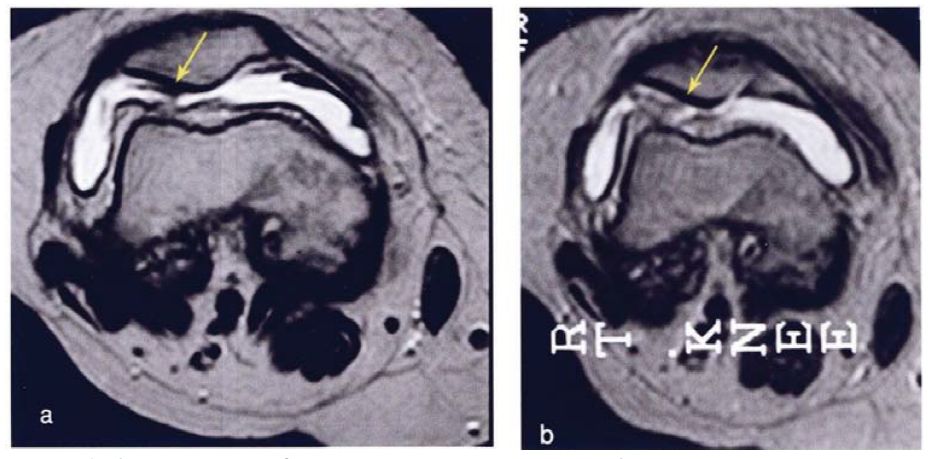

研究结果:关节内注射骨髓间充质干细胞6个月后,疼痛、功能状态和步行距离均提高。6名治疗组中3名患者在治疗前后的MRI比较可以看出,该治疗对于改善软骨厚度,修复组织延伸超过软骨下骨,以及减少软骨下骨的水肿是非常显著的。

上图a示意治疗前软骨,b为治疗后6个月软骨,箭头所示为软骨修复位置。